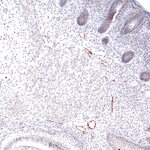

Immunohistochemical staining of a mouse small intestine using anti-Lyve1 (green) and anti-CD31 (red)

IHC-P: 1 : 150 gallery